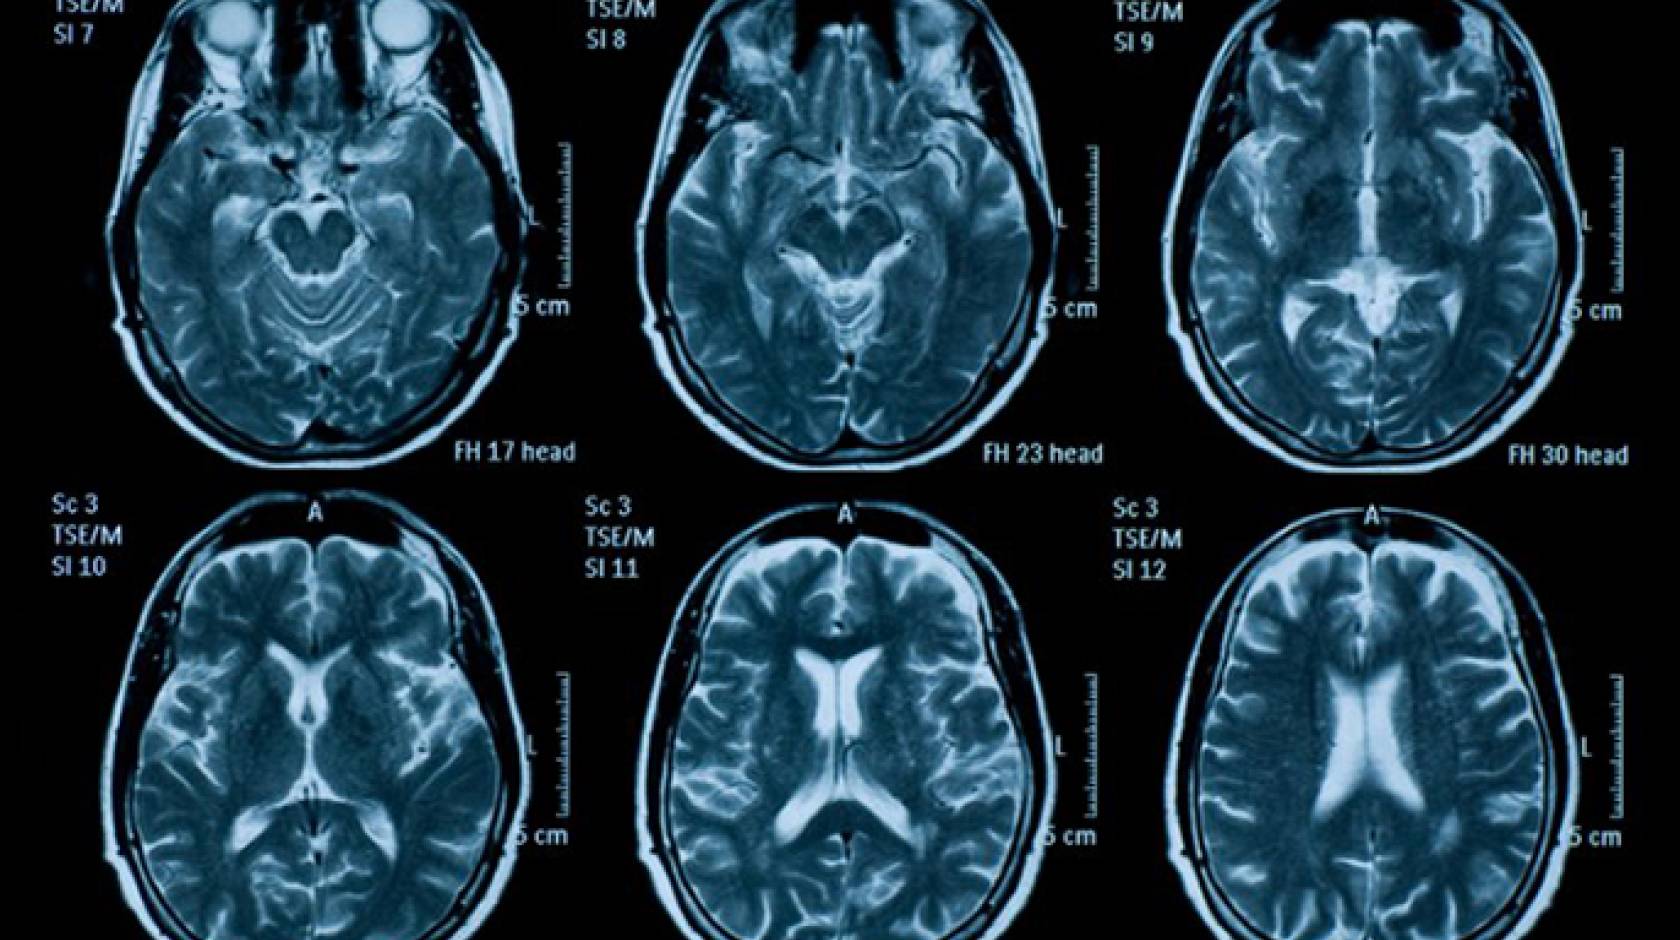

- Speed the diagnosis of traumatic brain injury, stroke or aneurysm by applying state-of-the-art artificial intelligence technology to computed tomography (CT) scanning (principal investigator: Pratik Mukherjee, UC San Francisco).